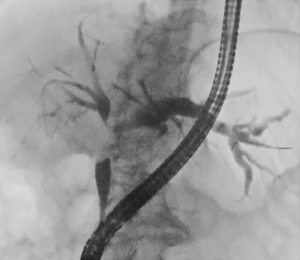

●症例1:IgG4-SC(70歳代、男性)(図2)

本症例は、IgG4値は37.1mg/dLの正常値であり、IDUSでは表面に若干凹凸が見られ、良悪性の鑑別は困難であった。生検の結果、病理学的な悪性所見はなく、IgG4の免疫染色も陰性であった。しかし、狭窄が強いにもかかわらず黄疸がほとんど見られなかったため、ステロイド治療を行った結果、1か月後に改善した。

図2 症例1:IgG4-SC(70歳代、男性)